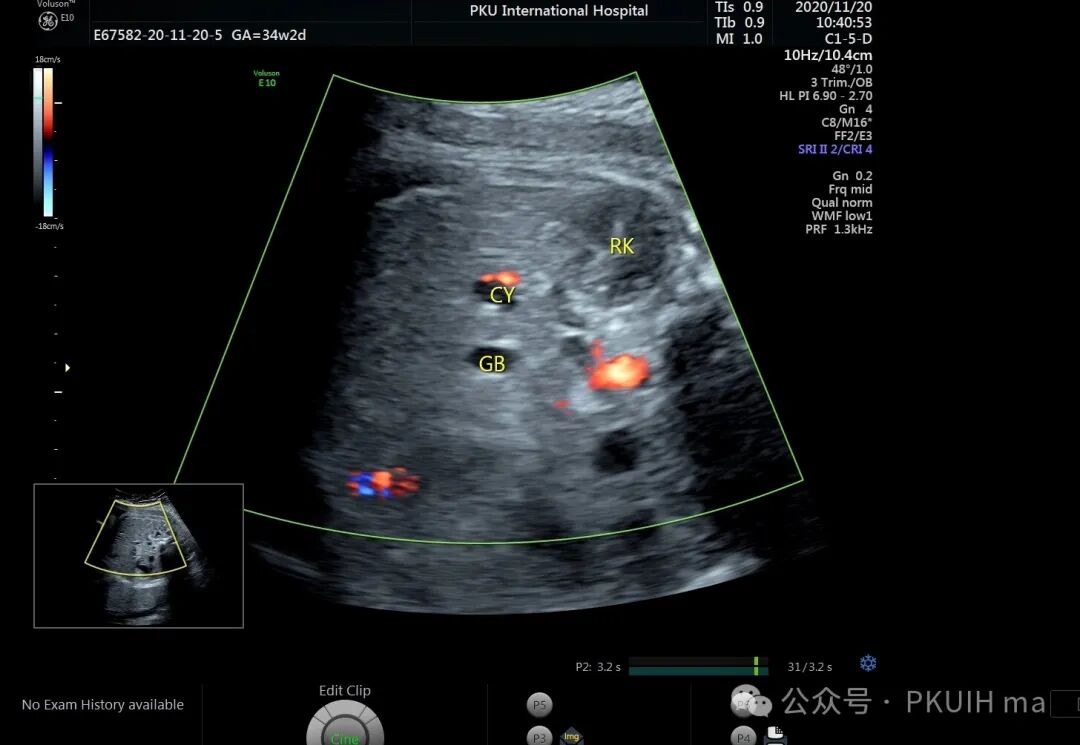

上图是一个孕晚期发现胎儿脾囊肿,在随后的观察中囊肿无明显变化。本例是一个脾实质内的囊肿,很容易和肾上腺囊肿鉴别。一般脾囊肿少见,肾上腺囊肿多见,且多大于脾囊肿,位置更靠近脊柱。